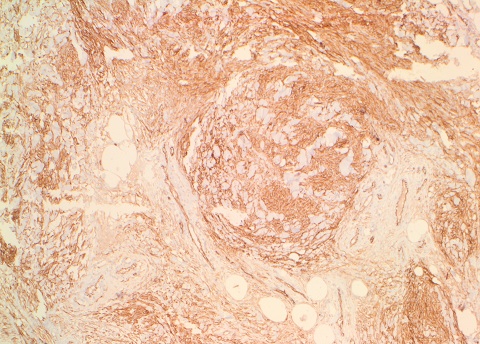

Immunohistochemistry:

The tumor cells were strongly positive for CD34, ER and PR.

Immunohistochemistry:

The tumor cells were strongly positive for CD34, ER and PR.